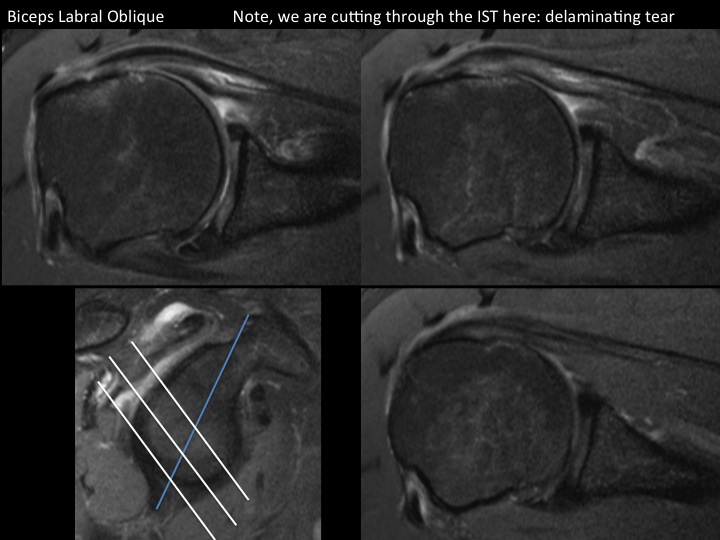

There is diffuse thinning of the suprapinatus tendon with full thickness tear posteriorly; the myotendinous jxn is retracted but there is little supraspinatus atrophy. There is a contiguous partial articular surface delaminating tear of the IST extending to the myotendinous jxn, best demonstrated in the BLO sequence. Axial images show partial articular surface delaminating tear of the subscap (note the extreme ER of the arm) with medial subluxation of the LHBT as there is a type 3 Bennett biceps pulley lesion. There is a low lying os acromiale with a subacromial enthesophyte and degen changes at the synchondrosis. Reference article.